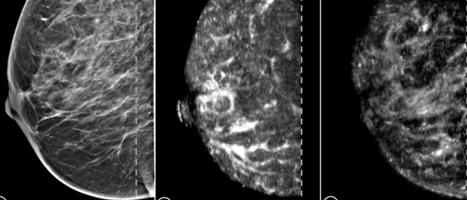

2. Las imágenes obtenidas por ecografía (ECO) y mamografía convencional y mamografía digital son ampliamente utilizadas.

Es obligatorio recordar que la ecografía no elimina la necesidad de mamografía aunque resulta muy útil en las mujeres embarazadas, con implantes mamarios o que no pueden hacerse, por cualquier motivo, la mamografía. La resonancia

magnética se indica en mujeres jóvenes, tiene limitaciones como cualquier otra técnica y no logra detectar todos los tipos de esta neoplasia. La tomografía computarizada (TAC) es útil para el rastreo de metástasis y valoración de la respuesta al tratamiento.

Es una forma efectiva de reducir por su utilidad para detectar el cáncer de manera temprana y tratarlo en esta etapa de la enfermedad. La mamografía es la piedra angular del tamizaje permite detectar tumores antes de palparlos o presenten síntomas. En el Ecuador la Estrategia Nacional recomienda hacerla cada 2 años en mujeres de 40 a 69 años de edad. Para mayores de 70 años depende de los antecedentes personales y familiares o de la indicación médica. Es de esperar que esto se cumpla. En menores de 40 años la conducta a seguirse depende de los factores de riesgo genéticos que de existir justifican una consulta con el especialista, si no los tiene se debe mantener una autoexploración mensual y consulta clínica anual.